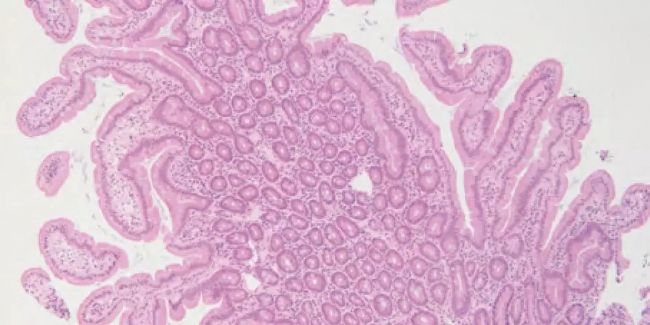

A. 內(nèi)窺鏡活檢 (H&E)脫水時(shí)間過(guò)長(zhǎng), 組織變得很脆,導(dǎo)致大量的

切片裂痕,而且切片技術(shù)不好會(huì)加劇這個(gè)現(xiàn)象;